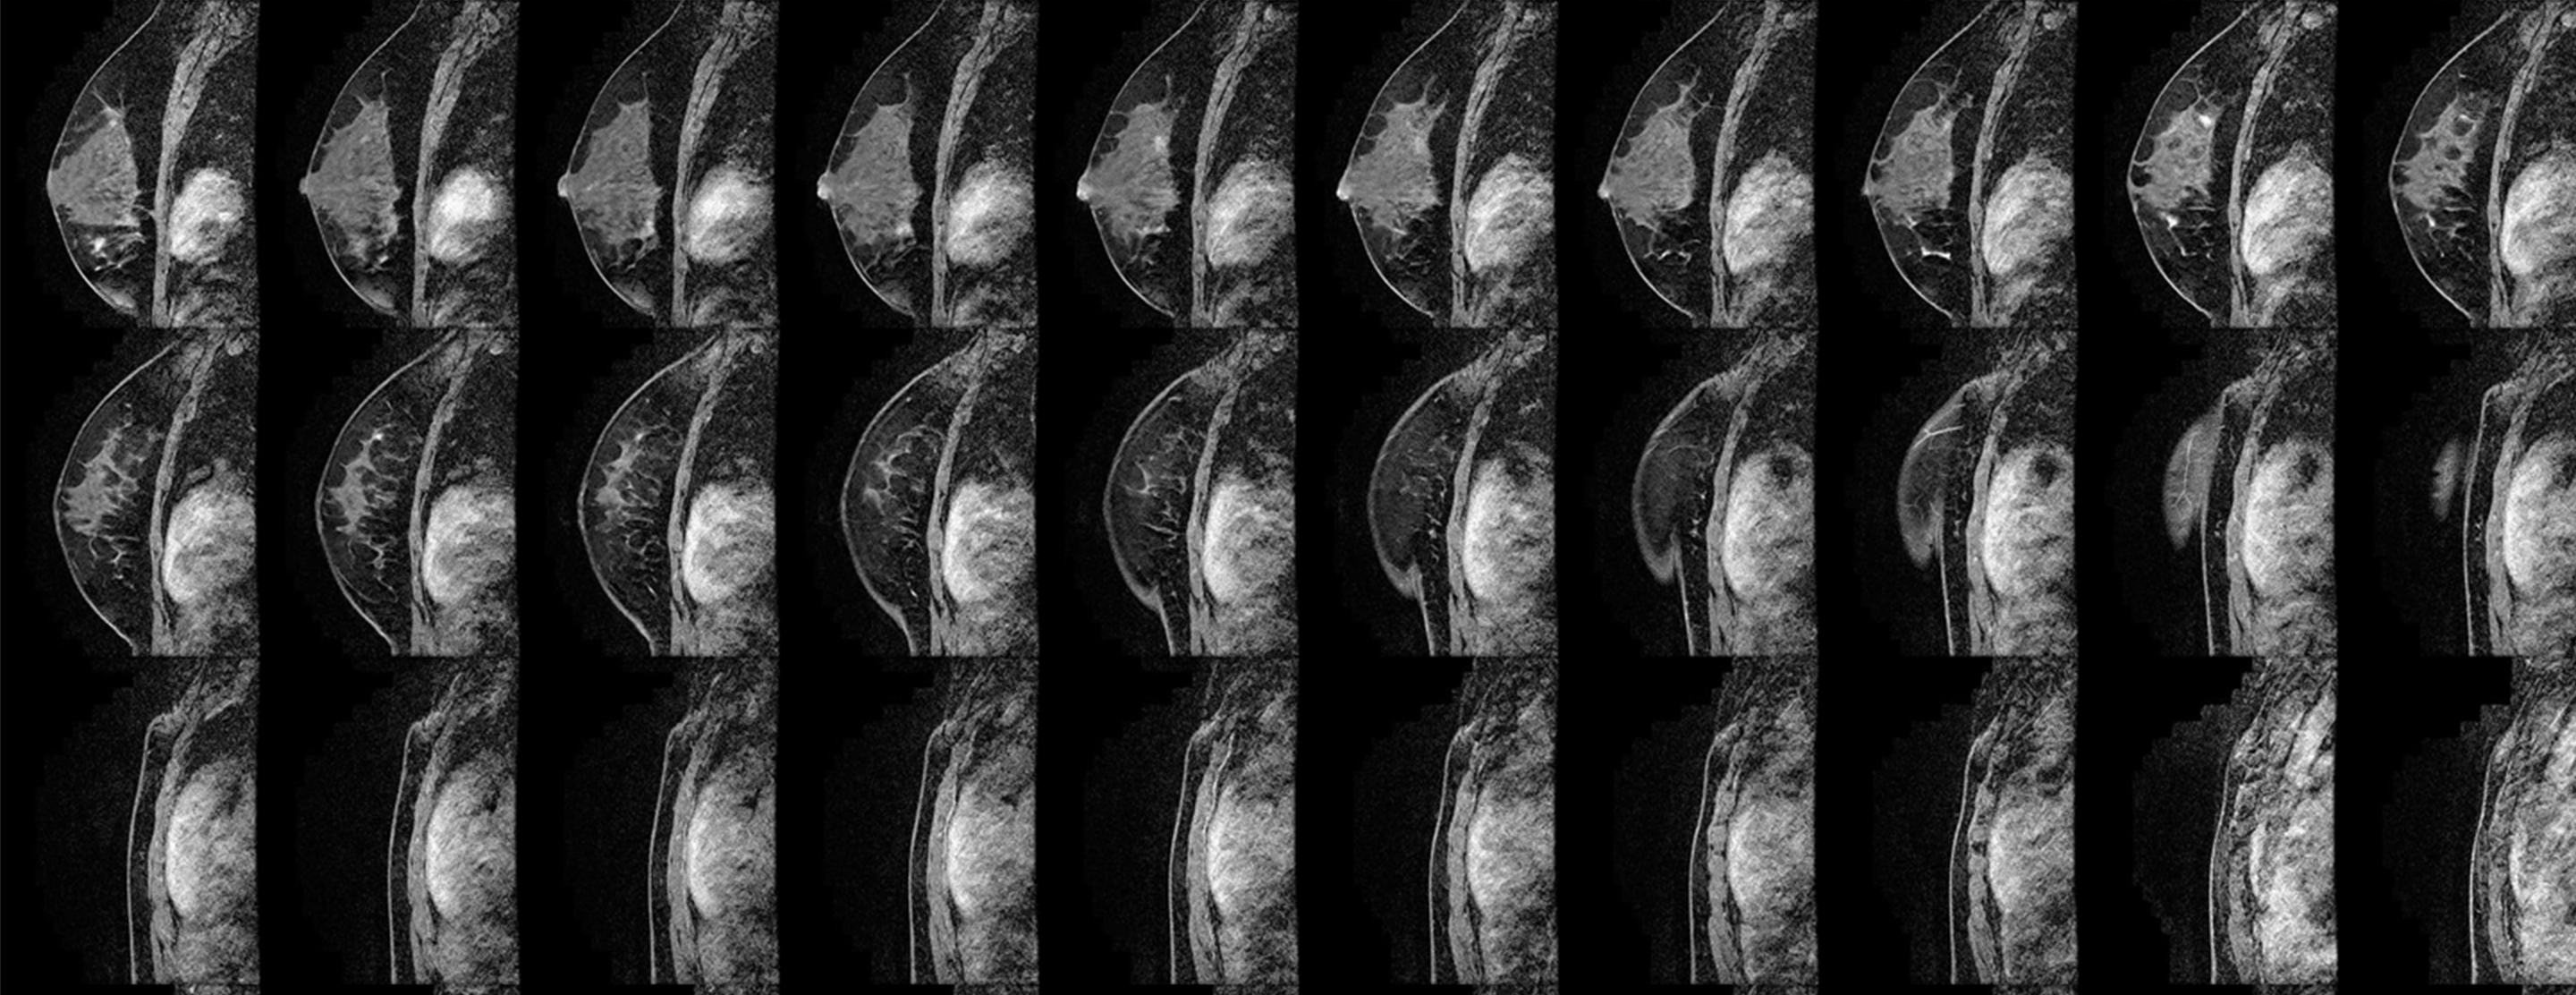

- Breast magnetic resonance imaging (MRI). This type of MRI scan can reveal abnormalities that aren't visible through mammography or ultrasound. Each scan produces hundreds of images.

The American Cancer Society recommends that certain women with an especially high risk of developing breast cancer have an MRI scan along with their yearly mammogram. A breast MRI is noninvasive, with no radiation exposure. But breast MRI is an evolving technology and shouldn't replace standard screening and diagnostic procedures, such as in-clinic exams during a regular checkup, self-exams, mammograms and biopsies.